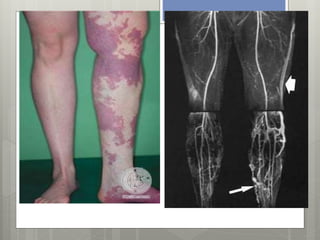

 Parkes Weber:

 Se caracteriza por eritema cutáneo con múltiples fístulas art

eriovenosas subyacentes, en asociación con el tejido blando

y la hipertrofia del esqueleto de la extremidad afectada (Mu

lliken y Young, 1988).

Angioma cutáneo mucinoso.  Nevus vascular plano y homogéneo.  Color rojo-vino.  Afecta la cara.  Se asienta sobre el párpado.  Región frontal ipsilateral al angioma pial.

• 84.

 Con frecuenciael angioma afecta a la hemicara completa.  Puede extenderse al cuello, tronco y extremidades de for-ma uni o bilateral.  Con frecuencia afecta la hemicara completa y puede exten derse al cuello, tronco y extremidades de forma uni o bilate -ral.  Los miembros inferiores se afectan más que los superiores.

• 85.

 Puede involucrar:  Mucosa de los labios.  Paladar.  Lengua.  Mejilla.  Faringe y laringe: en estos casos puede ocasionar sangrados.  Las partes blandas de la cara pueden estar hipertróficas, con menos frecuencia; partes duras, subyacentes (huesos, dientes)  Generalmente unilateral. Puede ser bilateral.  Extensión extrafacial más frecuente cuando el angioma es bila teral (53%) que cuando es unilateral (10%).

• 87.

 El nevusfacial está presente desde el nacimiento y no cambia de aspecto con la edad.